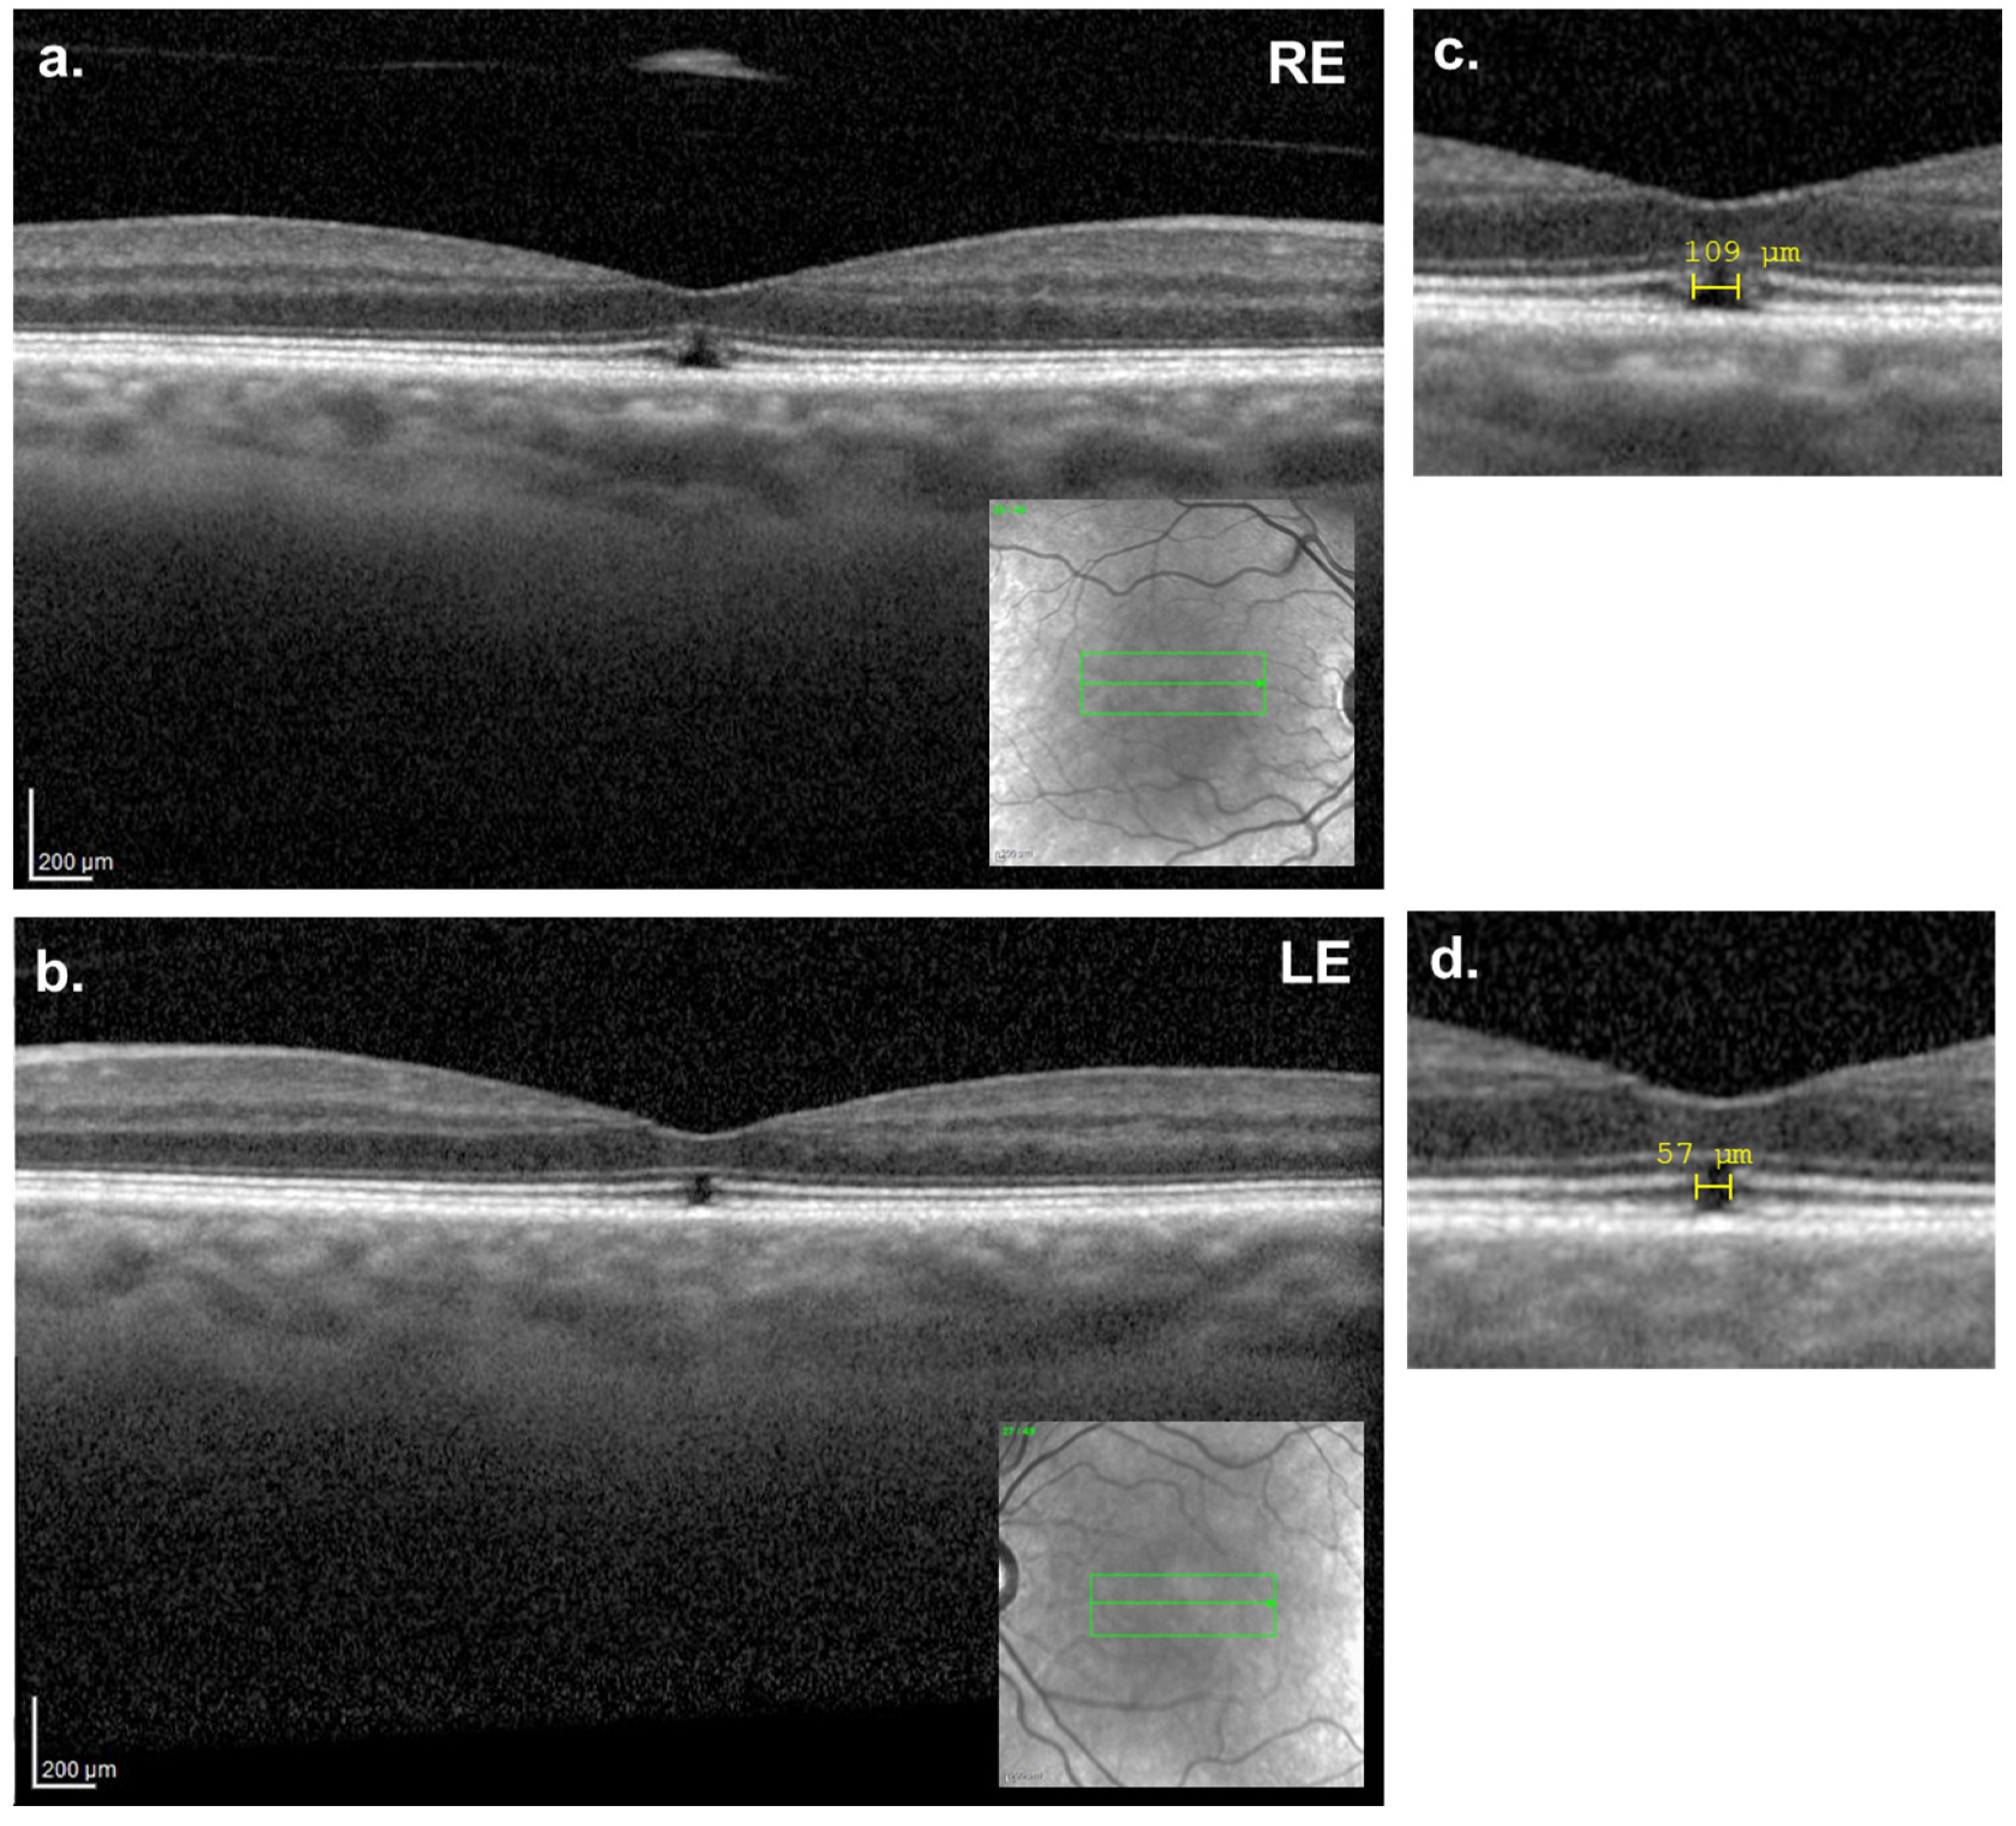

Bilateral Simultaneous Full-Thickness Macular Holes: A Case Report with Spontaneous Resolution

2. Case Presentation